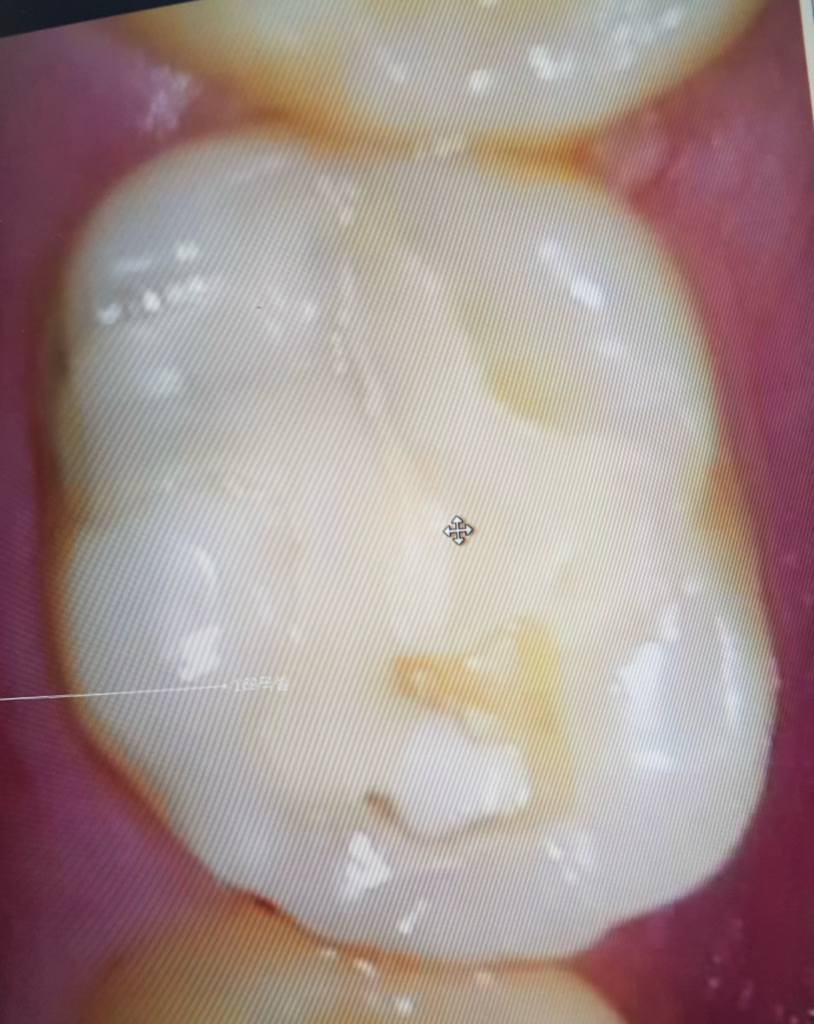

충치로 보이지는 않습니다. 치과에서 지켜보자고 하셨고 증상이 없으면 계속 지켜보면 될 것 같습니다.

수복한 재료에 누수가 생기게 되면 사진과 같이 색깔이 다르게 보일 수 있습니다. 이런 경우에는 보통 크라운이라는 보철 치료로 해당 부위를 치료해 준다면 누수가된 부위를 치료할 수 있을 것으로 생각됩니다

사진상으로 정확한 확인이 어렵습니다. 색상이 변한 경우 충치나 착색의 가능성이 있으며, 보다 정확한 상태 확인 및 치료를위해 치과 진료를 받길 권합니다.

두번째 사진의 치아에 보이는 음영의 경우 충치인지 해당 사진만 보고는 판단이 어렵습니다. x-ray 사진을 찍어보고 판단해봐야 합니다. 일단, 증상이 없다면 아주 깊은 충치이거나 심각한 상황은 아닐 것이라고만 추측됩니다.